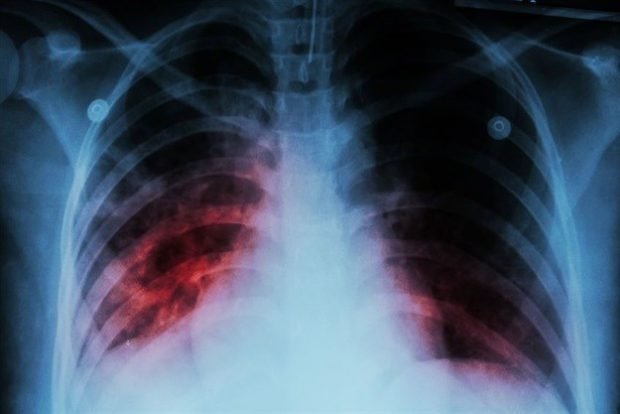

FDA Approved Medicine Offers New Hope For TB Sufferers

Until quite recently, people suffering from highly drug-resistant tuberculosis had poor treatment options and a poor prognosis. However, a new…